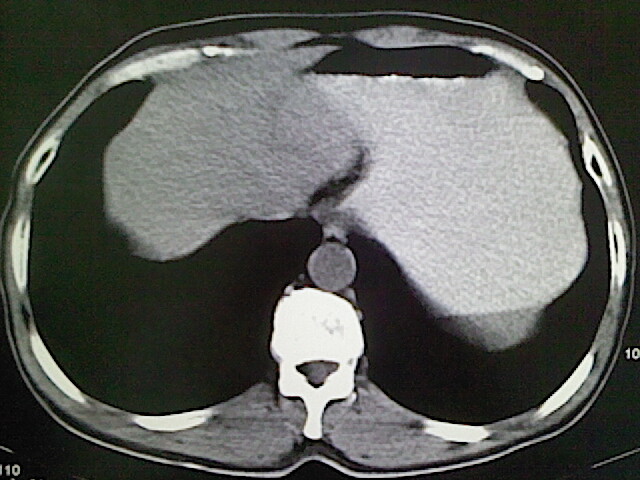

标题: CT18630:男,54岁,乙肝,大家看怎么样? [打印本页]

男,54岁,乙肝,大家看怎么样?

肝脏的要有增强敢说话

未见明确异常;建议必要时行ct增强扫描检查。